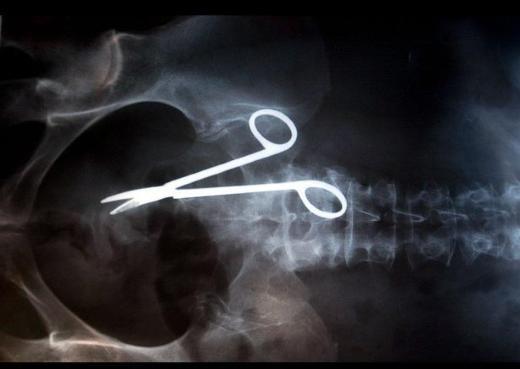

1. <p>Kimileri doktor hatası, kimileri de kaza... Huffington Post, dünyanın en garip tıbbi görüntülerini bir araya getirdi.</p>    Bu görüntü, Fransa'nın Lyon kentinde yaşayan Anne isimli bir kadına ait. Genç kadın, geçirdiği ameliyatın ardından bir türlü karın ağrılarından kurtulamayınca, doktorların rahminde ameliyat makası unuttuğu ortaya çıktı. Hatta o makas, kadının göbeğini deldi.

Bu görüntü, Fransa'nın Lyon kentinde yaşayan Anne isimli bir kadına ait. Genç kadın, geçirdiği ameliyatın ardından bir türlü karın ağrılarından kurtulamayınca, doktorların rahminde ameliyat makası unuttuğu ortaya çıktı. Hatta o makas, kadının göbeğini deldi.